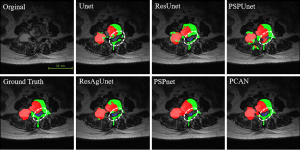

Under the same configuration environment and dataset, a comparative training was conducted on three advanced baseline network methods [Unet (38), ResUnet (47), and PSPnet (42)], as well as three autonomously improved networks based on the foundational architecture (ResAgUnet, PSPResUnet, and PCAN). Figure 5 shows the convergence of training loss values for different networks across various epochs. Among them, the Unet exhibited the slowest loss convergence speed, requiring approximately 50 epochs to approach the loss values of other networks. The training loss convergence speed of the PSPnet showed a significant improvement compared to Unet, demonstrating that the pyramid scene parsing (PSP) module enhances the feature learning capability of the network in small-sample learning tasks. Additionally, the training loss convergence speed of ResUnet also improved considerably compared to Unet, indicating that the residual module facilitates better feature learning. Furthermore, the loss convergence speed of ResAgUnet showed further improvement over ResUnet, indicating that the attention module enhances the network’s feature learning capability even more. The training loss convergence speed of PCAN was close to that of ResAgUnet, inheriting the feature learning advantages of both the PSP module and the attention module.

The segmentation of the spine, spinal cord, bone tumors, and background in target images directly affects the extraction of target features and classification performance. To evaluate the segmentation capability of the PCAN, we compared its segmentation results with other traditional methods, as detailed in Table 1.

PCAN gets the best MPA of 0.819 and the best MIOU of 0.711. MIOU, mean intersection over union; MPA, mean pixel accuracy; PCAN, pyramid cross-attention network; Se, sensitivity; Sp, specificity.

Among these, the Unet shows the lowest performance in terms of MPA and MIOU, with values of 0.789 and 0.677, respectively. ResUnet, which integrates residual modules to enhance feature filtering and transmission capabilities, achieves slight improvements in both MPA and MIOU compared to Unet. ResAgUnet, built on top of ResUnet, incorporates an attention module to enhance target segmentation capabilities, leading to a noticeable improvement in target recognition over ResUnet. PSPnet, which utilizes a PPM, shows slightly lower MPA and MIOU compared to ResAgUnet. PSPResUnet, which combines both residual and PPMs for feature recognition, demonstrated an improvement in target segmentation performance over the previous two methods.

The PCAN includes PPM, serial dual pooling, and cross-attention modules, which achieve improvements in the segmentation of large objects with complex internal textures. Its target recognition and segmentation performance exceeds other networks, with an MPA of 0.819, MIOU of 0.711, average sensitivity of 0.823, and average specificity of 0.922. Figure 7 shows the comparison of multi-target segmentation results of different networks, including the ground truth.